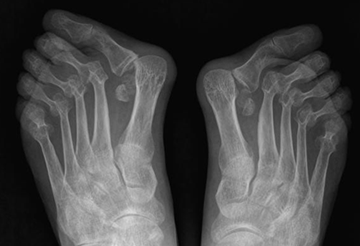

Fig 133. Artropatía reumática.

A: Rx AP de pies. Signos de osteopenia, con subluxación de las articulaciones tarsometatarsianas y ausencia de osteofitos.